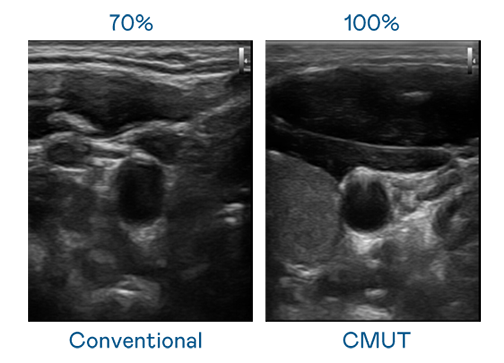

CMUT 技術是一種用電容式微機電元件來產生超音波訊號的技術。與傳統 PZT 壓電式技術相比,CMUT 頻寬增加 30%,更寬頻的超音波訊號讓影像解析度大幅提升,是實現高影像品質醫療超音波掃描、促進精準醫療發展的關鍵技術。

超音波影像的解析度高低,首先取決於探頭能發出的訊號頻寬。AG真人 CMUT 可提供高清晰的超音波訊號,提供高頻寬、高靈敏度、影像紋理細節更高的超音波影像,協助醫護人員縮短影像判讀時間及利用精準的醫療影像進行診斷。